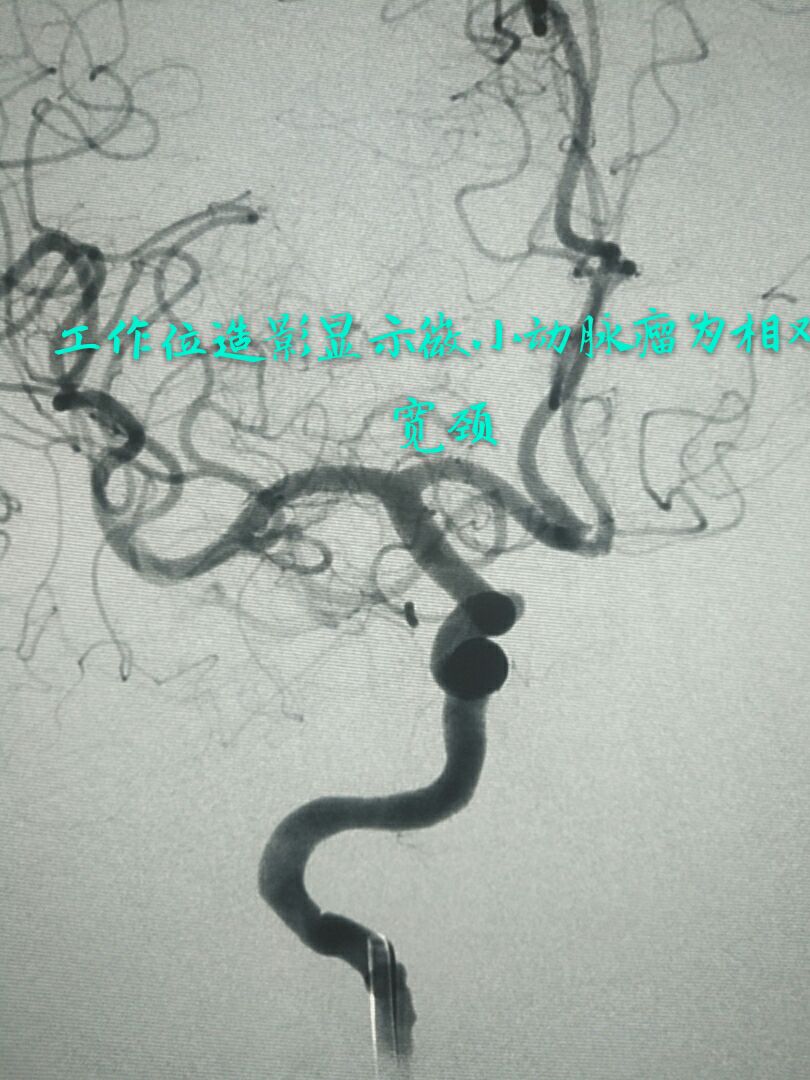

病例七:眼动脉段破裂微小动脉瘤,相对宽颈,呈锥形

支架辅助下用小弹簧圈致密栓塞动脉瘤